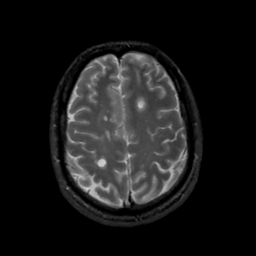

MR Study #1, February 10, 1991 -- Slice #38